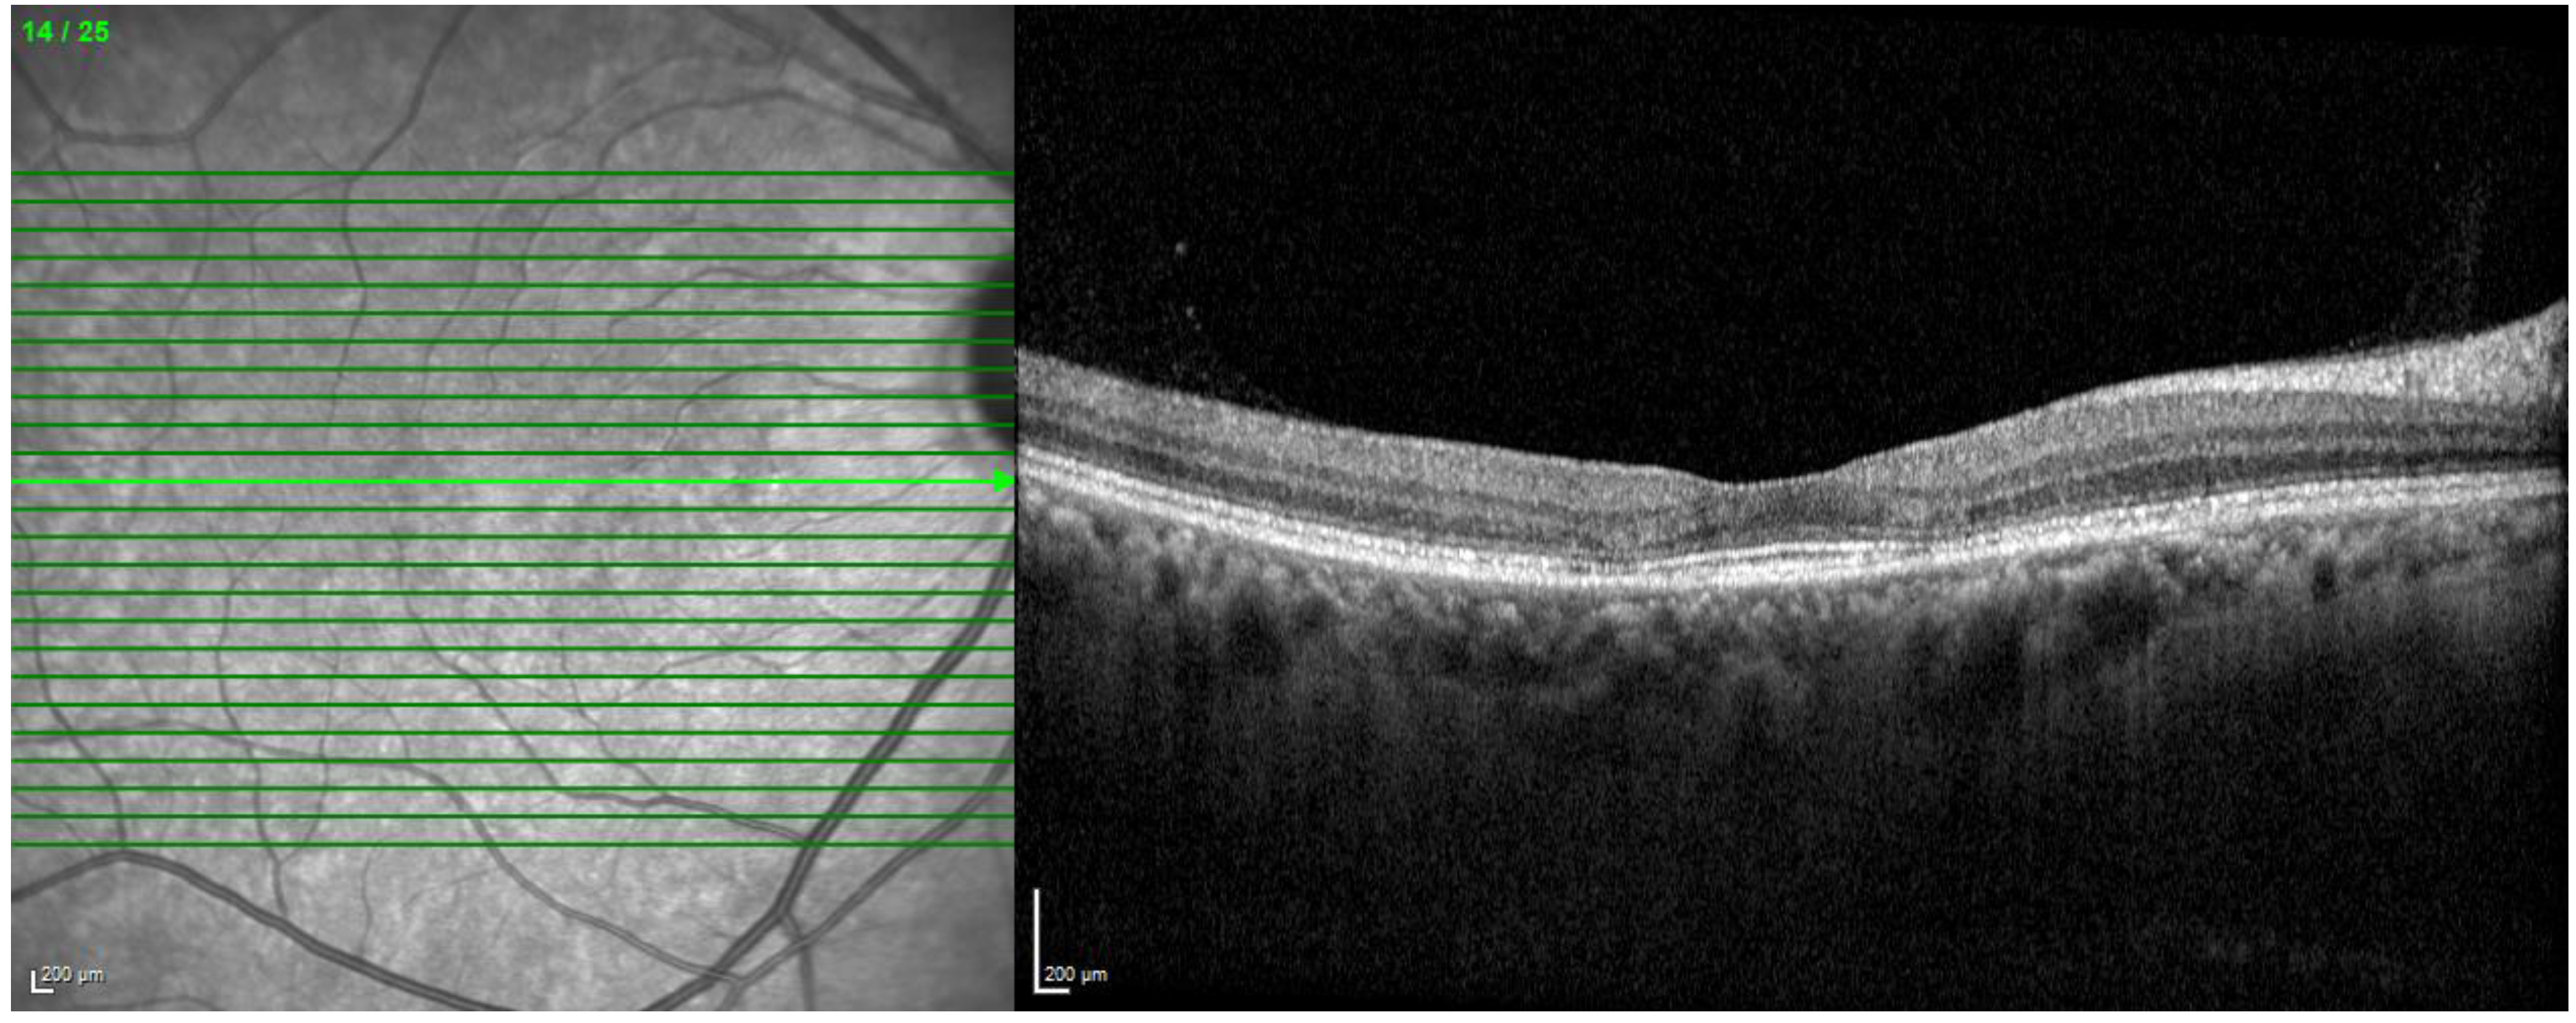

- Wolff, B.; Matet, A.; Vasseur, V.; Sahel, J.-A.; Mauget-Faÿsse, M. En Face OCT Imaging for the Diagnosis of Outer Retinal Tubulations in Age-Related Macular Degeneration. J. Ophthalmol. 2012, 2012, 542417. [Google Scholar] [CrossRef]

- Leitgeb, R.A. En Face Optical Coherence Tomography: A Technology Review [Invited]. Biomed. Opt. Express 2019, 10, 2177–2201. [Google Scholar] [CrossRef]

- Lau, T.; Wong, I.Y.; Iu, L.; Chhablani, J.; Yong, T.; Hideki, K.; Lee, J.; Wong, R. En-Face Optical Coherence Tomography in the Diagnosis and Management of Age-Related Macular Degeneration and Polypoidal Choroidal Vasculopathy. Indian J. Ophthalmol. 2015, 63, 378–383. [Google Scholar] [CrossRef] [PubMed]

- Ahn, S.J.; Joung, J.; Lee, B.R. En Face Optical Coherence Tomography Imaging of the Photoreceptor Layers in Hydroxychloroquine Retinopathy. Am. J. Ophthalmol. 2019, 199, 71–81. [Google Scholar] [CrossRef]